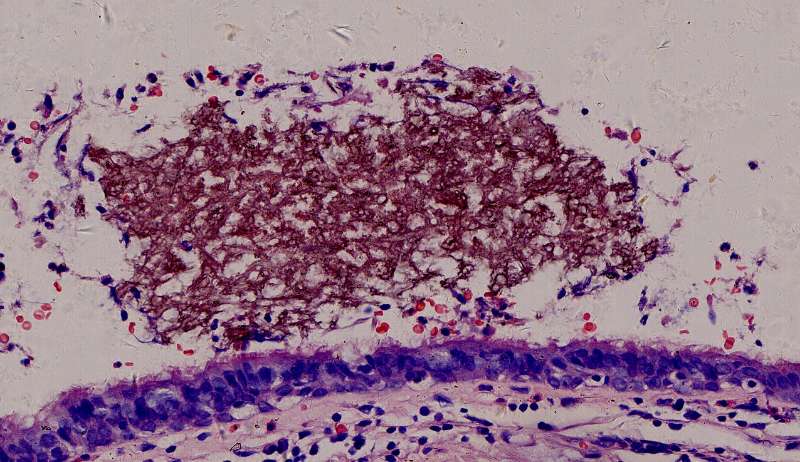

为什么有含铁血黄素呢? 曲霉菌容易使周围出现出血。太多含铁血黄素,吞不完 剩下一点曲霉菌,看看:

菌丝都快死了,隐约可见 这些红黑色点点是什么? 王:中性粒细胞,挺多的。这也是曲霉菌感染的一个特点。

刚才的曲霉菌是这里?王:是的,这里有残留菌丝 第二例曲霉

曲霉菌孢子很少见到,基本都是菌丝团,这里也是支气管扩张区,菌丝团偏黄褐色,也快死了。

蓝色圈圈是菌丝团?红色箭头是淋巴细胞?这是空腔边缘吗?王:是的,红箭头也可能是中性粒细胞。 红箭是支气管粘膜有炎症。

这里的菌丝形态清楚,下图小圆空的结构挺多,我理解为管状菌丝的断面